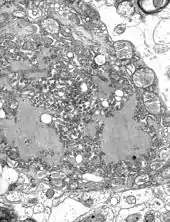

Le virus de la rage est un virus neurotrope, en particulier du système nerveux central. Il se multiplie dans le cytoplasme des cellules nerveuses où il forme des inclusions visibles en microscopie optique : les corps de Negri. Ce neurotropisme explique pour partie les troubles observés, comme l'hydrophobie, appellation historique de la rage[2], et présente dans 95 % des cas humains[3].